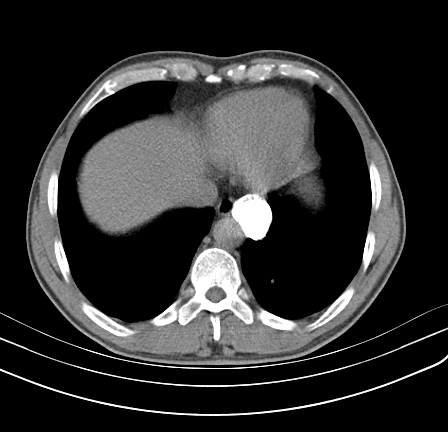

以下是引用影像孺子牛在2009-5-20 23:18:00的发言:[br]左侧后心膈角处类椭圆形钙化灶,最常见的是淋巴结钙化,但太大了不支持,其它如食管囊肿钙化、实性畸胆瘤等。何东西钙化真不好定。

以下是引用zbp537在2009-5-20 20:52:00的发言:[br]钙化灶,来源不好说。